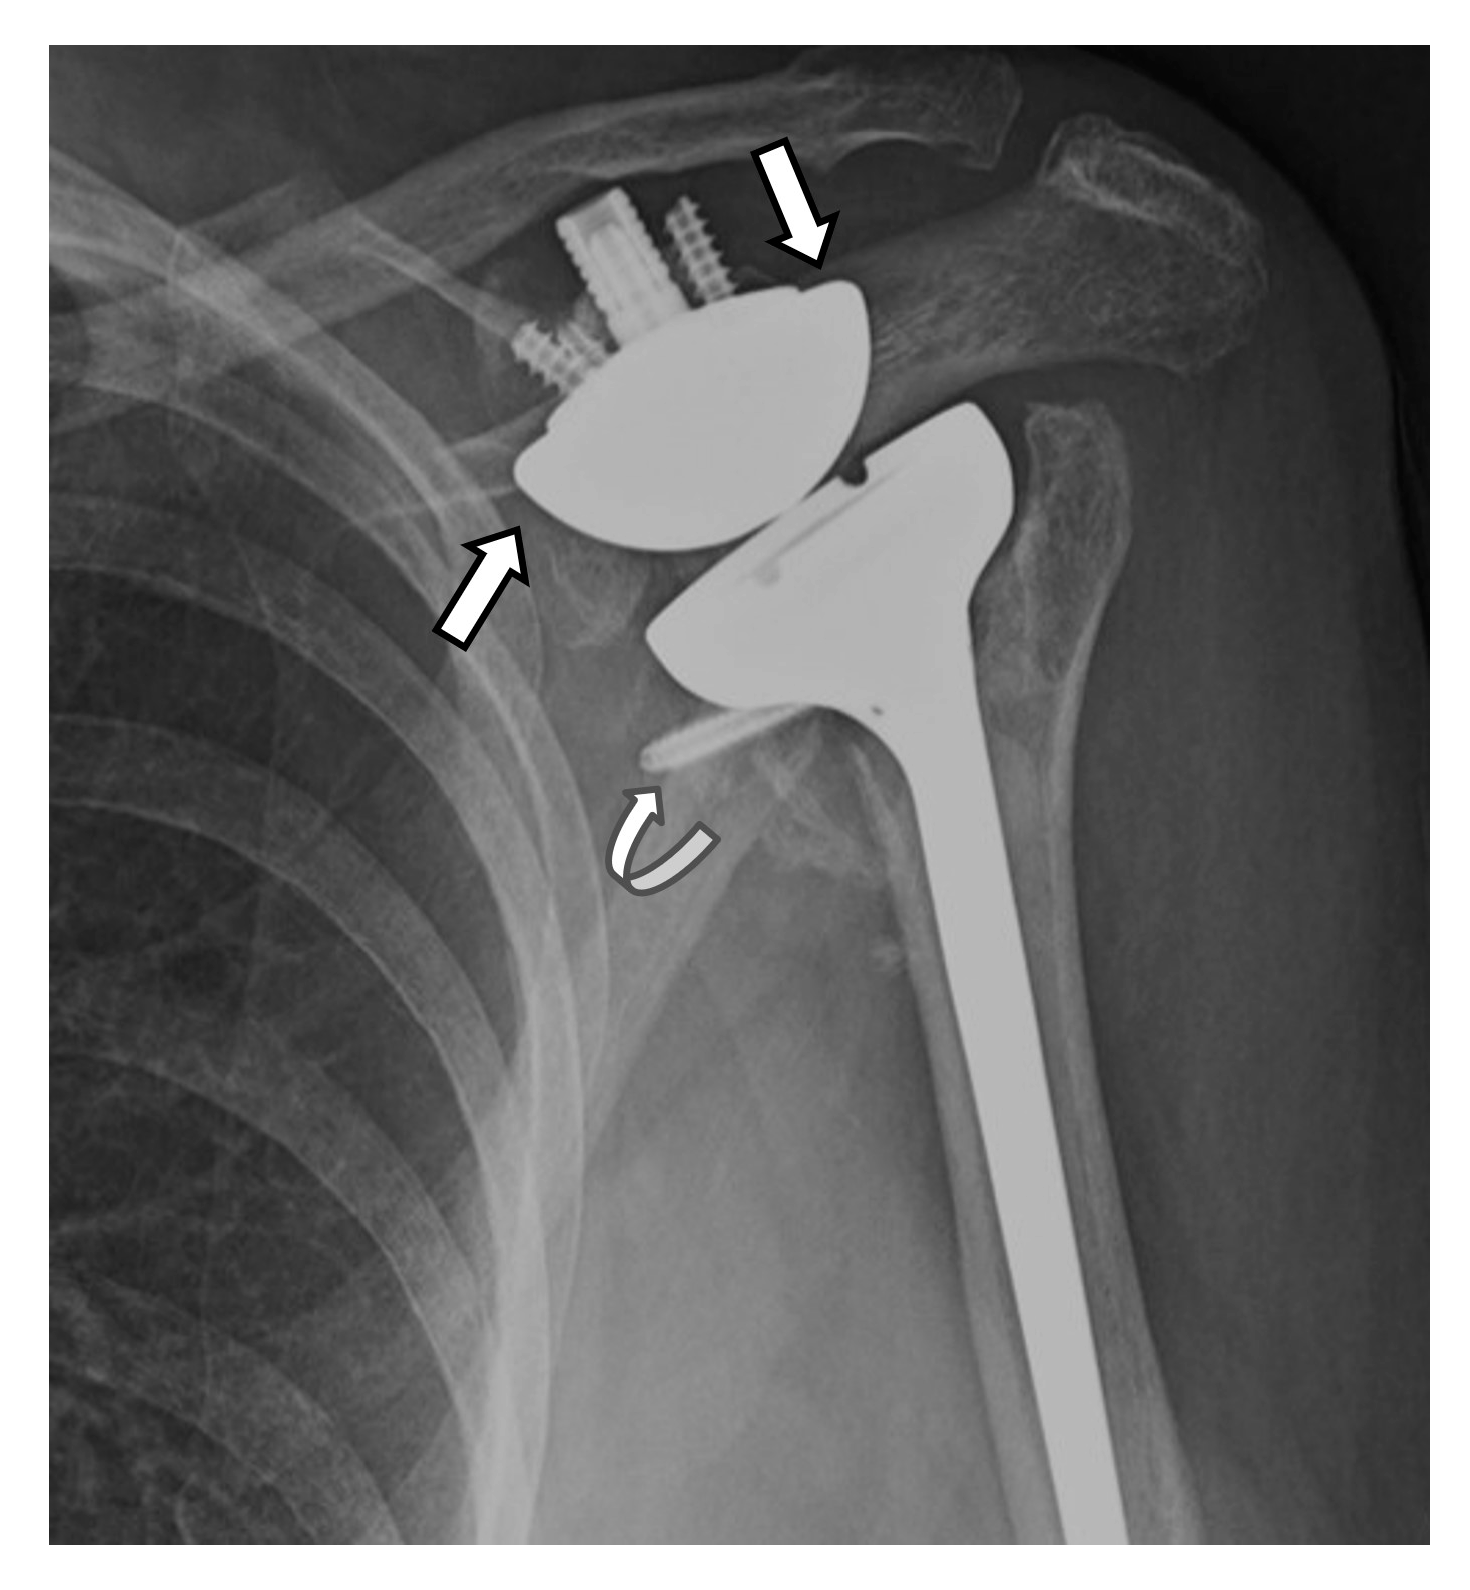

4.3. Unique Complications

5.2. Reverse Arthroplasty

Reverse Total Shoulder Arthroplasty (RTSA)